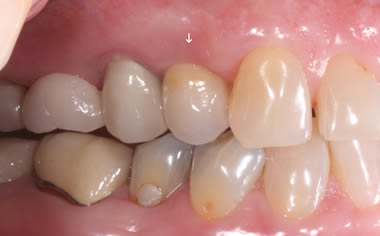

More back teeth replaced by dental implants

Case Three (2 images)

Case Four (4 images)

Case Five (4 images)